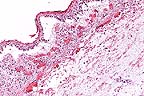

Epithelial necrosis, acute inflammation, and cleft formation in the rumen of a calf with chronic arsenic toxicosis. (HE, 200X, 54K)

Marked acute inflammation and hemorrhage in the rumen of a calf following chronic ingestion of an arsenic compound. (HE, 200X, 64K)

History: Several calves and cows were acutely ill. Several died in the last 4 months. This calf was alive when sent to the laboratory but died on the way. A bottle of MSMA herbicide (monosodium methanearsonate) was eventually found to have a pin-hole leak and had been dripping into a meal supplement in a storage shed.

Gross Pathology: The rumen had dark red blotches diffusely across the epithelial surface but the serosa was grossly normal. The abomasum contained milk curds and its mucosa was diffusely fiery red and a few Haemonchus sp. were present. The reticulum and omasum were grossly normal. The intestine and colon contained brown watery material and their mucosae were dull brown with a red tinge.

Laboratory Results: Rumenal contents were negative for arsenic. The liver was positive for arsenic at 1.92 ppm.

Contributor's Diagnosis and Comments: Superficially necrotizing subacute rumenitis (and omasitis) due to arsenic toxicity.

Whole blood from another sick cow had elevated arsenic at 0.14 ppm. Normal bovine liver arsenic levels are 0.004-0.4 ppm. High levels are 1.0-5.0 ppm and acute toxic levels are 2.0-15 ppm. Normal blood arsenic is 0.03-0.05 ppm and acute toxicity occurs from 0.17-6.7 ppm. Arsenic is rapidly cleared from the body (half-life 1.5 days). It is directly corrosive to the GI tract but also inactivates the sulfhydryl groups of oxidative enzymes within capillary endothelial cells; the liver, kidney and intestine are most sensitive. Capillaries become more permeable and the muscle layer of small arteries relaxes. The GI mucosa may slough away from underlying edema. In this calf, the abomasum and intestine were normal except for congestion and the other organs were normal microscopically. Fungal stains on the rumen and omasum were negative. The omasal lesions (not submitted on most slides) were much milder and more multifocal than those in the rumen.

AFIP Diagnosis: Rumen: Rumenitis, necrotizing, acute, diffuse, severe, with hemorrhage, edema, and focal arteritis, mixed breed, bovine.

Conference Note: Animals may be poisoned with arsenic through ingestion or percutaneous absorption. The most common sources of arsenic are insecticides and herbicides containing sodium arsenite, lead arsenate, or arsenic pentoxide. Poisoning occurs when animals gain access to recently sprayed pastures. Ore deposits frequently contain high levels of arsenic and poisoning may occur when pasture and drinking water are contaminated by exhaust from smelters. Other sources include wood preservatives and injectable preparations to control blood parasites.

In domestic animals, arsenic does not stay in the tissues very long. It is partially methylated in the liver and kidney and is rapidly excreted in urine, feces, bile, milk, saliva, and sweat. Arsenic may cross the placental and blood-brain barriers in small amounts. The milk from poisoned cows is toxic for humans and calves, but meat is considered safe for consumption.

The organs most susceptible to inorganic arsenic toxicity are the brain, lungs, liver, kidney, and alimentary mucosa. The lesions produced by acute poisoning can largely be explained on the basis of vascular injury. The lesions most commonly observed are severe congestion, edema, hemorrhage and vascular necrosis. Lesions in the stomach and intestines usually include intense congestion with edema, hemorrhage, and ulceration. Brain lesions usually include moderate, diffuse cerebral edema and petechiation. A peripheral neuropathy has been described. Chronic arsenic poisoning usually has the same anatomic distribution of lesions as acute poisoning. The application of arsenicals to the skin may result in a chronic dermatitis or, if absorption is rapid, systemic toxicity. The dermatitis is characterized by intense erythema, necrosis, and sloughing.